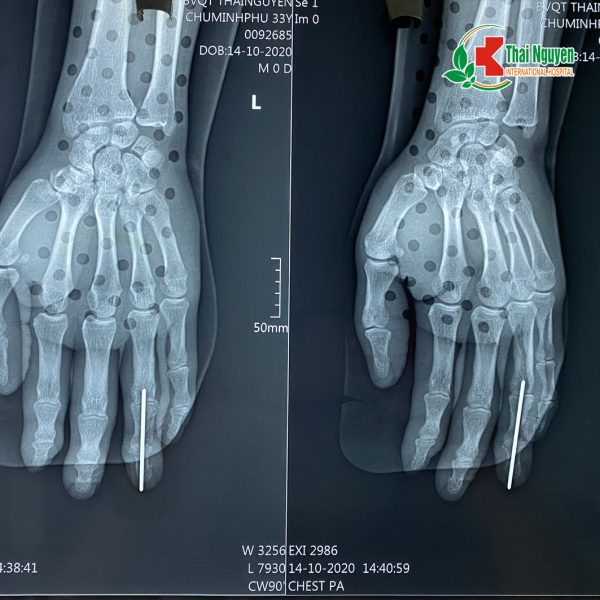

Hình ảnh chụp Xquang bàn tay của bệnh nhân Chu Minh.P sau khi đã phẫu thuật

???Các bác sỹ khoa Ngoại chấn thương đã tiến hành gây mê nội khí quản, thực hiện cắt lọc vết thương, xuyên 1 đinh kischner từ đầu ngón 4, cố định xương gẫy, khâu phục hồi điểm bám gân, xử lý các vết thương ở các ngón tay.